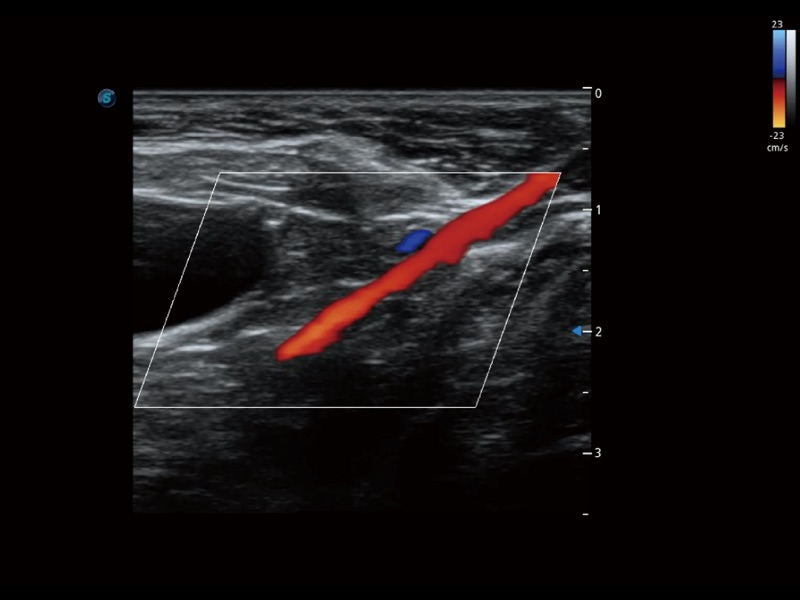

优异的基础图像

ProPet 70 全新的动物超声智能软件和丰富的探头群,为动物医生提供了高清晰度和精细分辨率的图像,无论在宠物、马科、畜牧还是实验室动物等应用中都可以轻松应对,为您的日常工作带来满意的体验。

(犬)髂动脉血流

(犬)胎儿主动脉弓立体血流